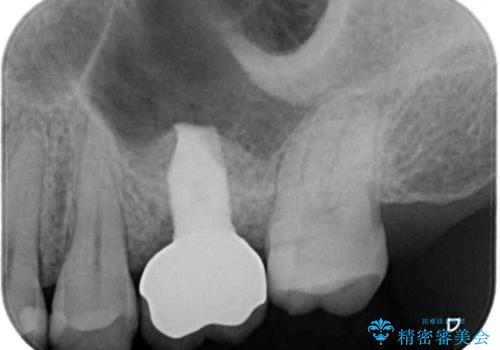

- 深い咬み合わせと前歯のデコボコ、奥歯の欠損を気にして来院された患者様です。

歯列矯正はインビザラインを使用し、矯正治療中の適切な時期に奥歯の欠損部位にインプラントを埋入することとしました。

矯正治療とインプラント治療を同じ歯科医師が担当することで、通常見られるような複数医院を行き来する煩雑さや、複数担当医の見解の違いによる治療の遅滞といった煩わしさは一切なく、スムーズに治療を進めることができました。